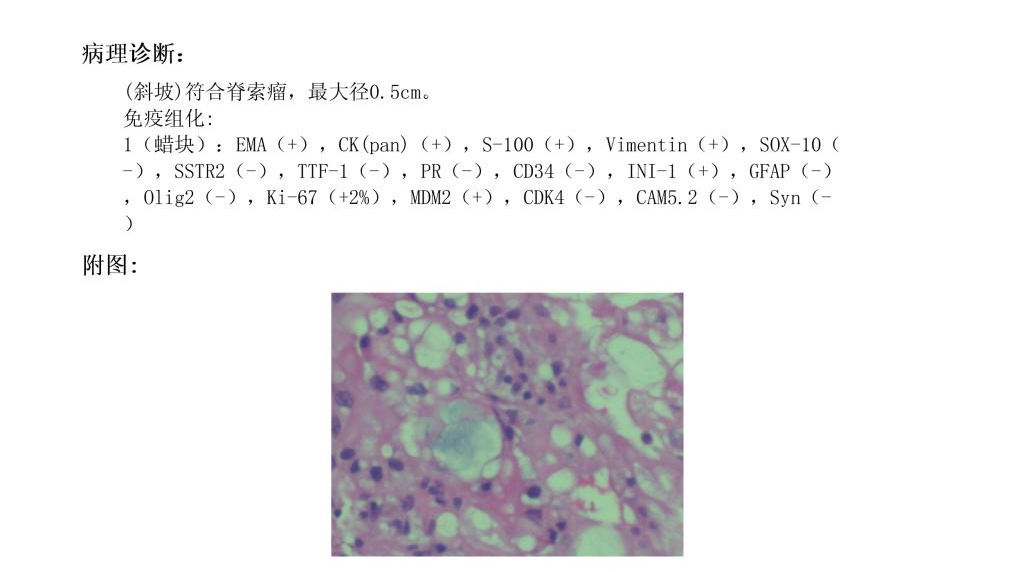

术后病理提示

那么,至此该患者所有的疑团均已解开,是一个生长于斜坡的微小脊索瘤侵蚀了骨质及硬膜,导致出现自发的脑脊液鼻漏,经过我们微创手术,目前患者已经平稳出院,恢复正常生活。

脊索瘤是一种罕见的、生长缓慢的、具有局部侵袭性及破坏性的肿瘤。脊索瘤是低度恶性的肿瘤,有高度的局部增长倾向。大部分脊索瘤侵犯骨质,生长于硬膜外,在肿瘤增大到一定程度后会侵犯以及突破硬膜进入颅内。此例患者肿瘤微小即侵犯了硬膜,在常规MR上不显影,较为少见,临床中容易忽略此类疾病,也提示我们在排查脑脊液漏原因的时候,一定要把肿瘤性因素考虑在内,避免遗漏。